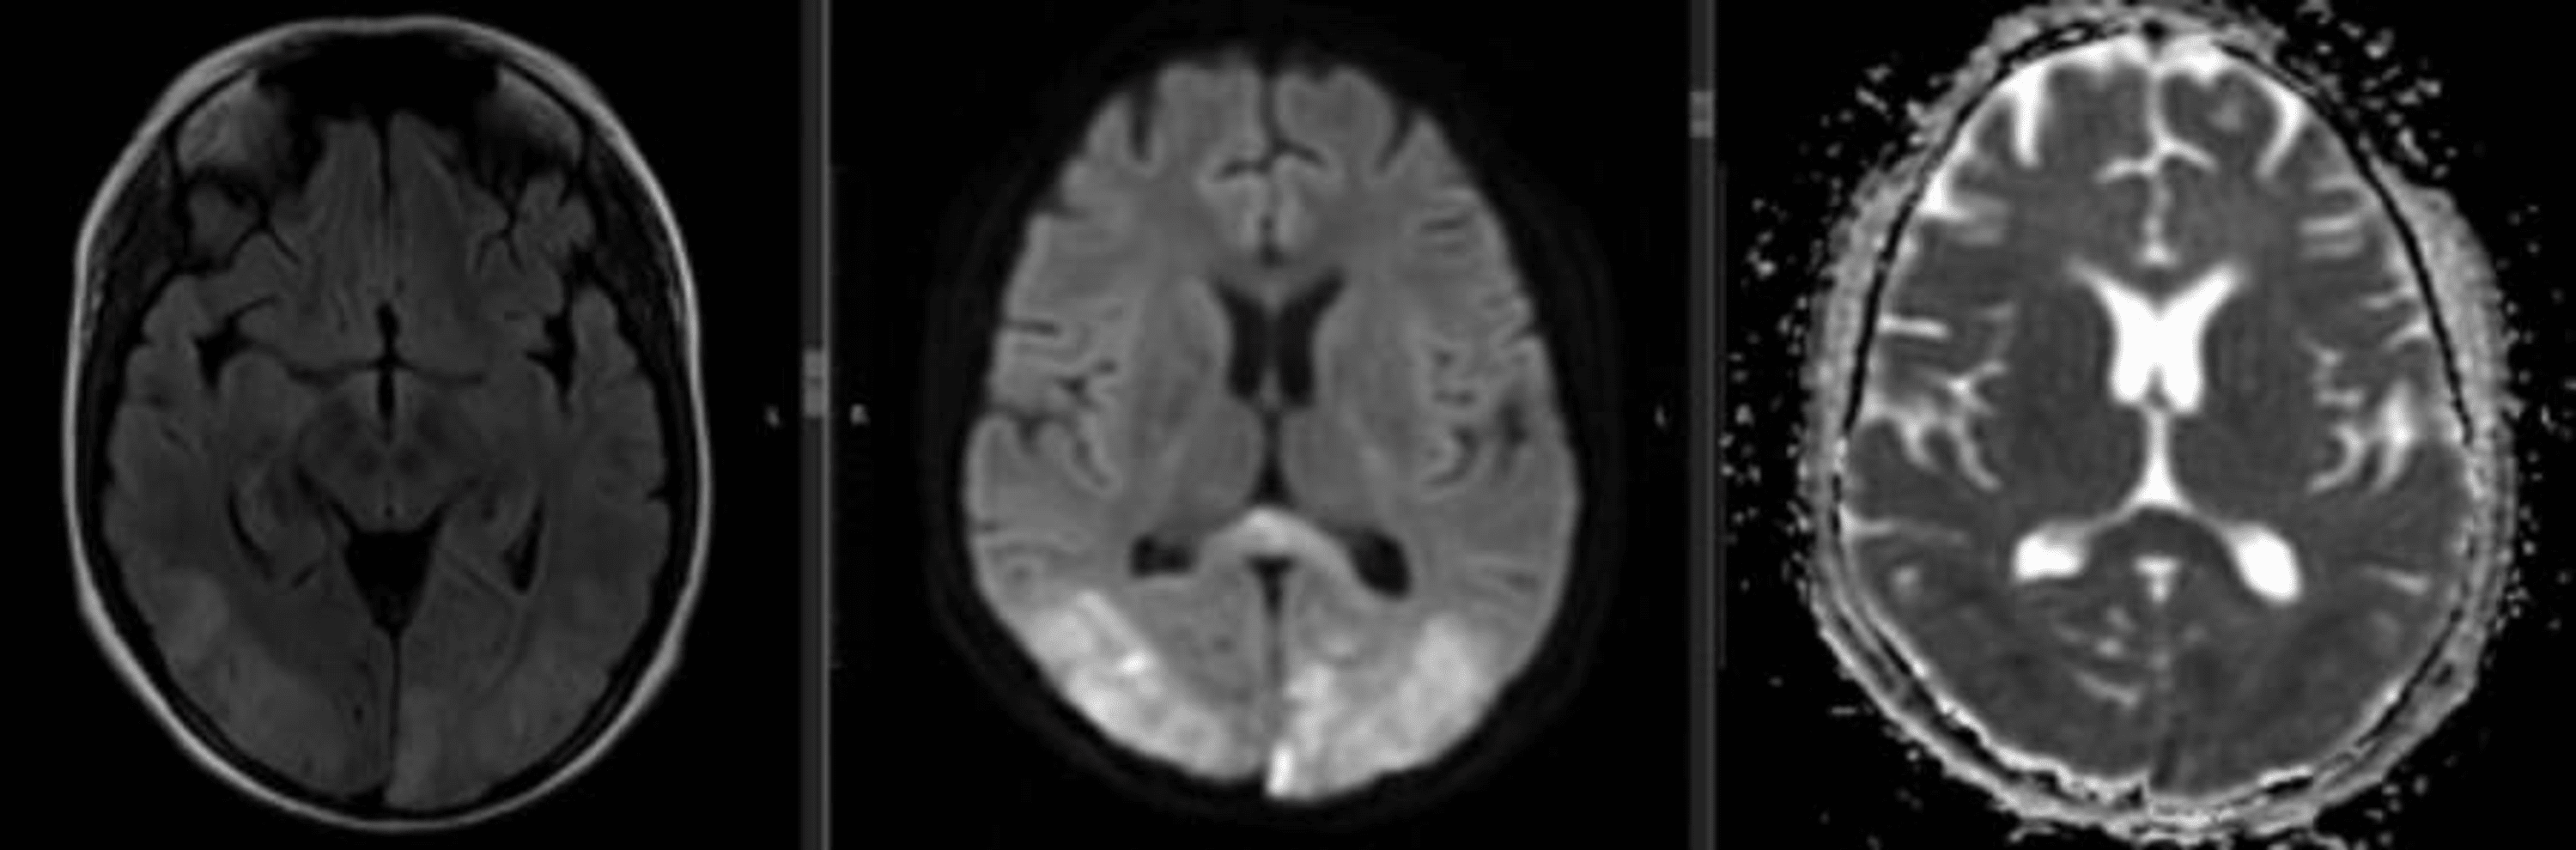

From www.semanticscholar.org

Figure 1 from Diffusion MR Imaging of Eclampsia Semantic Scholar Eclampsia Radiology We assessed the distribution and. Posterior reversible encephalopathy syndrome is associated with eclampsia. Clinical and neuroradiographic correlates and insights into the pathogenesis. It is considered a severe and life. Preeclampsia, defined as the new onset of hypertension, peripheral edema, and proteinuria after at least 20 weeks of gestation in a woman previously without. E levated l iver enzymes and. Eclampsia Radiology.

Figure 2 from Diffusion MR Imaging of Eclampsia Semantic Scholar Eclampsia Radiology We assessed the distribution and. It is considered a severe and life. E levated l iver enzymes and. Preeclampsia, defined as the new onset of hypertension, peripheral edema, and proteinuria after at least 20 weeks of gestation in a woman previously without. Clinical and neuroradiographic correlates and insights into the pathogenesis. Posterior reversible encephalopathy syndrome is associated with eclampsia. Eclampsia Radiology.